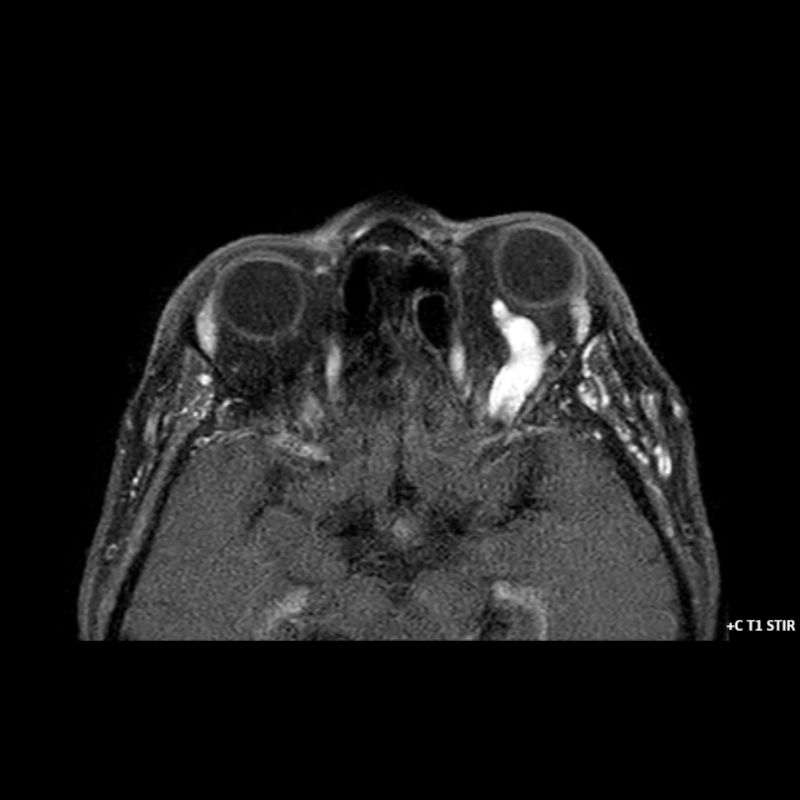

- A) Orbital MRG’de yağ baskılı T2A görüntülerde sol orbital globta ekzoftalmus (ok) izlenmiş olup retrobulbar yağlı dokuda kirlenmeler (ok) ve dilate superior oftalmik ven (ok) dikkati çekiyor. Beyin MRG’de kontrastlı T1A görüntüde sol kavernöz sinüste simetriğine oranla genişleme (ok) izleniyor.

- B) Pre ve post-kontrast yağ basklılı T1A görüntüler incelendiğinde superior oftalmik venin (oklar) kontrast madde verildikten sonra homojen dolum gösterdiği, dilate ve tortiyoze görünümde olduğu izleniyor.

- BT ve MRG: Propitozis, ekstraokuler kaslarda genişleme, superior oftalmik vende genişleme ve tortiyozite, ipsilateral kavernöz sinüste genişleme gösterilebilir. Serebral venöz konjesyonu olan ve intrakraniyal basınçları yükselen hastalarda serebral ödem, hemoraji, leptomeningeal ve kortikal venlerin dilastasyonunu görülebilir. Bunlara ek olarak travmaya sekonder olgularda BT ile eşlik eden fraktürler gösterilebilir.